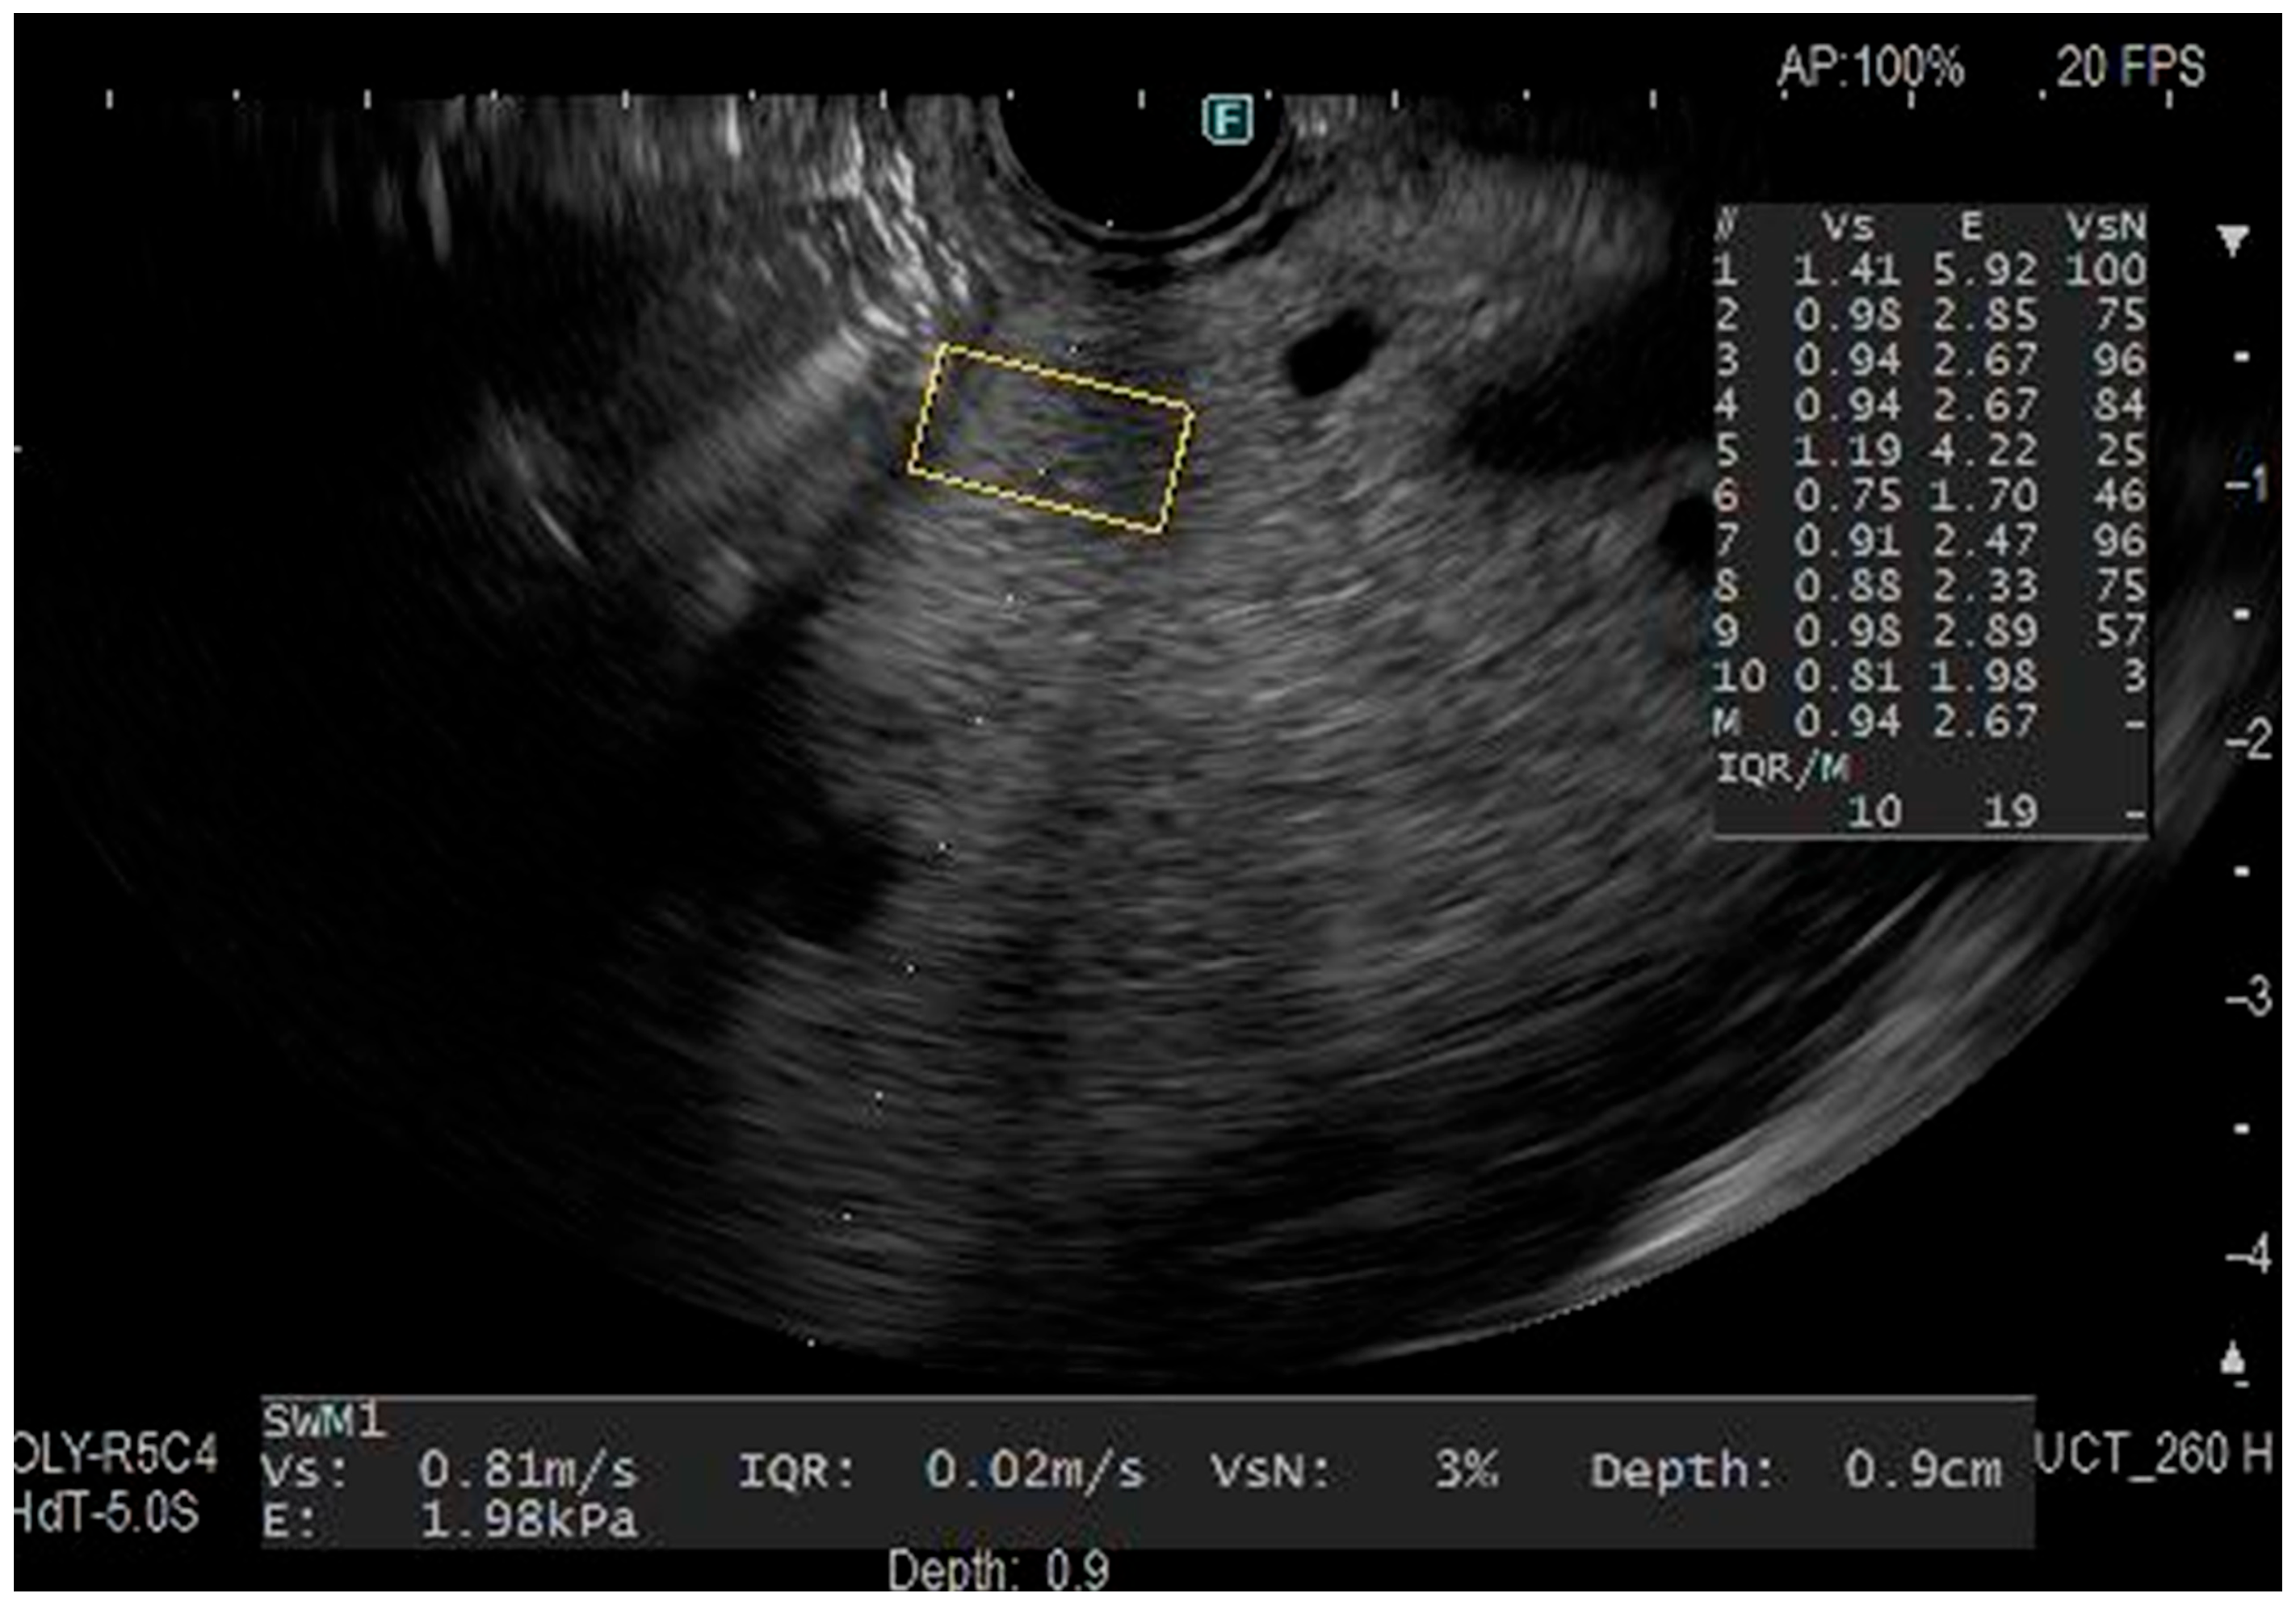

2.3. Endoscopic Ultrasonography Procedure and EUS-SWM